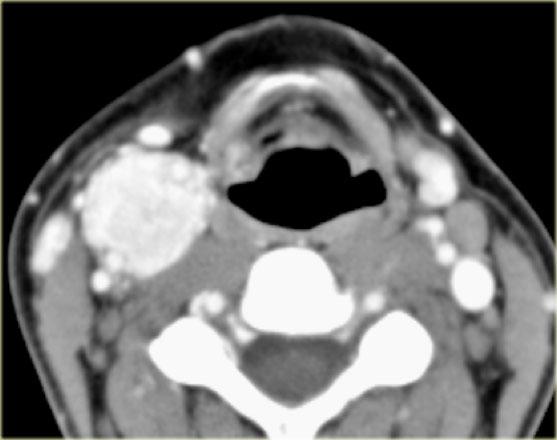

Bên trái là hình CT ở mức sụn giáp.

Có một khối không đều nằm trung tâm ở xoang lê bên phải.

Khối này nằm trong khoang tạng.

Ở vùng này, khối u thường gặp nhất là ung thư biểu mô tế bào vảy.

Chẩn đoán này đã được xác nhận qua sinh thiết.

Lưu ý khoang sau hầu (mũi tên vàng).

Đây là khoang ảo chỉ chứa một ít mô mỡ.